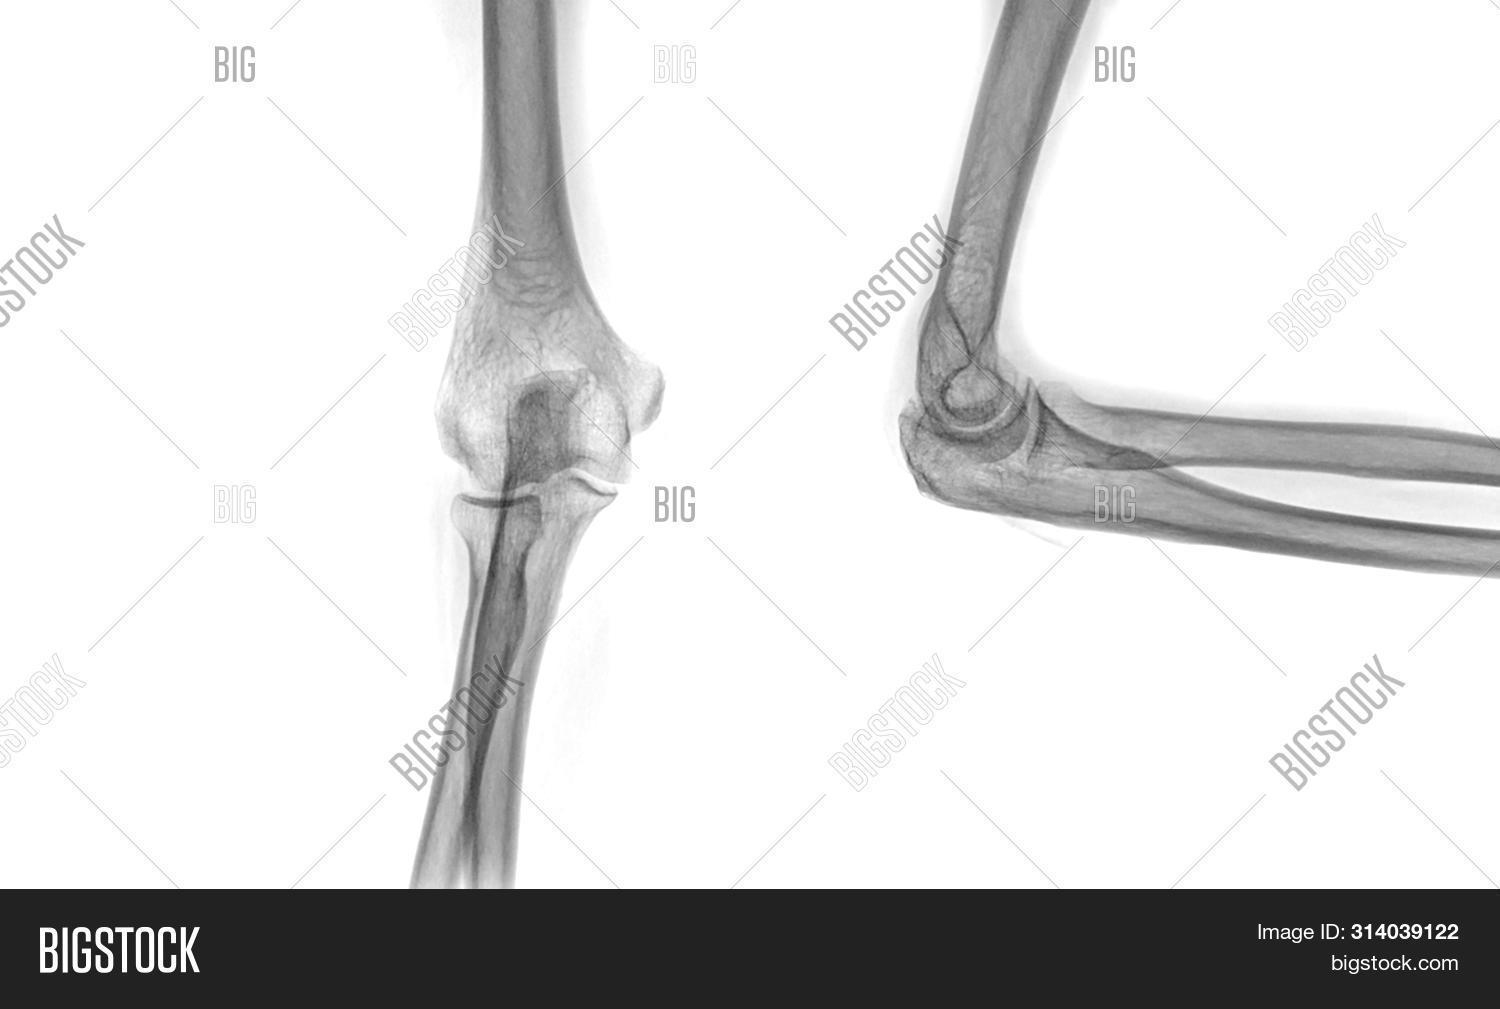

From www.bigstockphoto.com

Xray Elbow Image & Photo (Free Trial) Bigstock Elbow Imaging Rules an effective clinical decision rule to exclude fracture in acute elbow injury would prevent unnecessary radiography, and could reduce. Choosing a search strategy and utilizing it consistently is a helpful method to overcome common errors seen in diagnostic. Additional radiographic images should be included as indicated. optimal elbow radiographic technique requires the patient to tolerate, and cooperate with,. Elbow Imaging Rules.